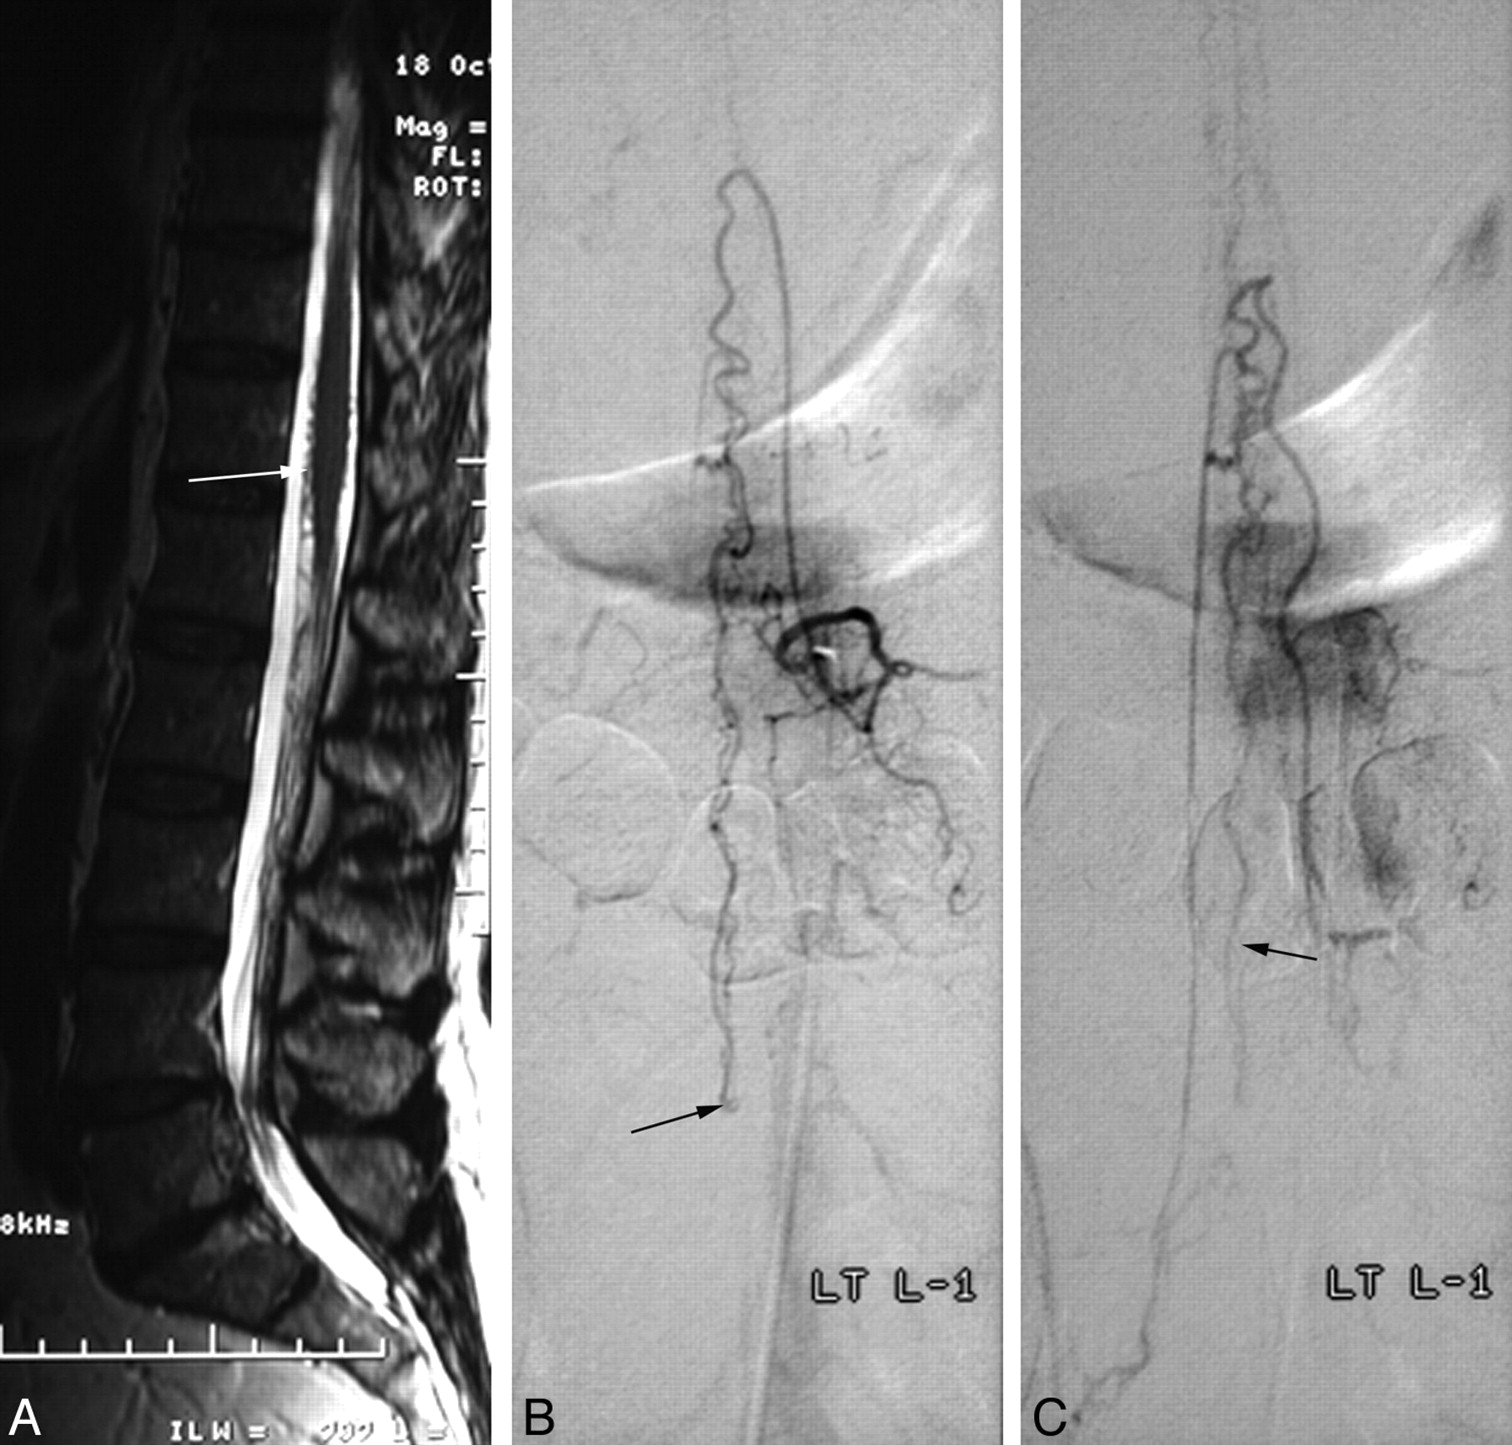

Spinal AVF of the filum terminale (patient 3). A, Sagittal T2-weighted image shows vascular signal-intensity voids with high signal intensity in the lower spinal cord and large signal intensity voids (arrows) on the filum terminale. B and C, Selective angiograms of the right L1 radiculomedullary artery represent an AVF on the filum terminale (L4 level, arrow in B). The feeder of this AVF is the anterior spinal artery and draining vein, which has 3 aneurysmal dilations (arrows in C) is the perimedullary vein running upward. D, A venous aneurysm and the proximal venous side of the AVF are embolized with detachable coils (arrow in D) and n-BCA

All fistulas were located between the L3 and L5 levels. Three patients had a single fistula with 1 feeder extending from the anterior spinal artery to a single draining vein in the filum. The dilated single vein reached the conus medullaris and drained into the anterior and posterior surfaces of the cord in 2 cases, but 1 fistula drained only into the anterior spinal vein. One patient with minor symptoms had venous drainage to the radicular veins to the right S1 and left L3 after reaching the spinal cord. Patient 3 (Fig 1) had a high-flow fistula with a dilated artery of the filum terminale draining to a single ectatic vein.

Among 4 patients, 2 (patients 1 and 2) underwent surgical clipping of the fistula, because the caliber of the anterior spinal artery was small and the course was tortuous (Fig 3). The other 2 patients (patients 3 and 4) underwent endovascular treatment. Patient 3, with a high-flow fistula, had a dilated radiculomedullary artery from the right L1 lumbar artery, which was easily catheterized with a 0.016-inch-inner-diameter microcatheter. The venous aneurysm and fistula were occluded with a combination of detachable coils and fibered coils. Patient 4 needed 2 stages of embolization. During the initial procedure, a 0.010-inch microcatheter was advanced to the feeding pedicle through the right L4 lumbar artery, and embolization of this pedicle was performed by using n-BCA. A control angiogram of the left internal iliac artery showed persistent filling of a portion of the nidus from the lateral sacral artery (Fig 2B). During catheterization of this second feeder, extravasation of a small amount of contrast was observed following a superselective angiogram. We decided to terminate the procedure and treat the rest in a second session. Postprocedural CT showed a small amount of contrast in the intradural space of the L4 level. The remaining nidus was embolized with n-BCA after 2 short pushable coils were placed in the artery of the filum terminale distal to the nidus to protect the anterior spinal artery axis. Complete obliteration of the malformation was achieved.